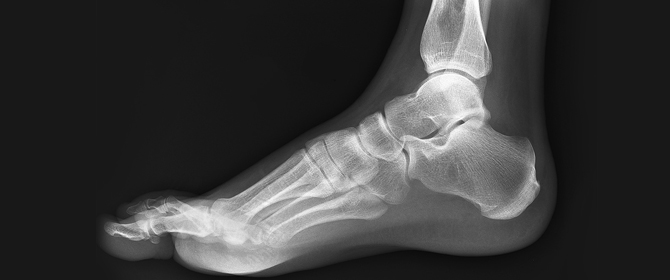

Our practitioners will then run through with you what will need to be done to help the problem and then you can ask questions about the treatment. Sometimes an x-ray exam is also needed so that the actual cause of the problem can be identified.

Post-Treatment Review. These allow the team to monitor your body and take place regularly to see how you’re going. If appropriate, x-rays are examined pre- and post-treatment to ascertain the amount of structural correction that has occurred.

Note: The above images show outcomes of foot mobilisation treatment combined with corrective exercise. It must be noted that these images are not meant to denote or even provide a guarantee that all clients will experience the same outcomes. Due to the different type of causes of foot and leg pain, results between clients can differ significantly.